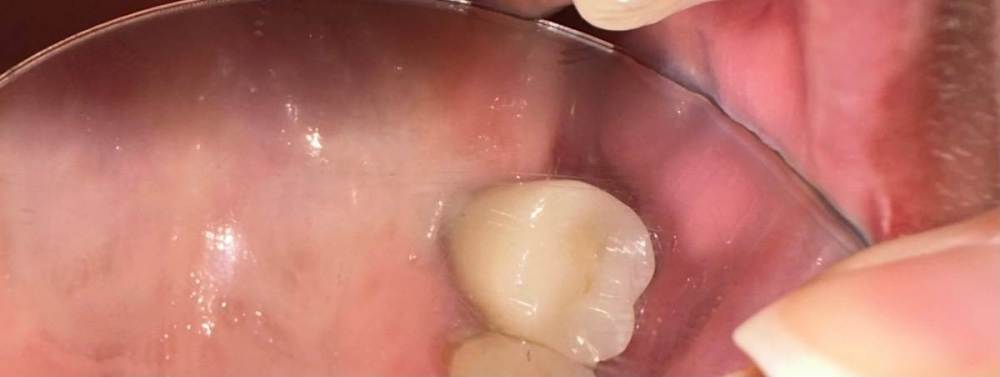

Mitt Опубликовано 29 октября, 2023 Поделиться Опубликовано 29 октября, 2023 (изменено) Здравствуйте. Ж., 39 лет. Так получилось, что мне нужно решить, что делать с имплантатом на месте верхней шестерки. А тк я не обладаю необходимой компетенцией, очень нуждаюсь в подсказках специалистов. Дано: 1. 2014-2015 гг - удаление зуба, синус лифтинг, имплантация с пластикой мягких тканей, установка коронки. 2. 2015 - 2019 гг - проблема контактов с рядом находящимися пятым и седьмым зубами, воспаление десны вокруг 5, имплантант, 7. Решалось путем композитных «накладок» на 5 и 7 зубы. 3. 2019 - 2023 гг - пластика мягких тканей, удаление 7 зуба с подсыпкой графта, еще штуки 3 или 4 пластики, включая вестибулопластику, временная коронка. 4. 2023 г - установка новой постоянной коронки, 5 месяцев тишины, с августа гной в районе имплантата (десна спокойна). Проблемы общие для всех временных периодов - тандем с пазухой и периодические ближе к постоянным боли разной интенсивности и локации (пазуха, 7 зуб, место от 7 зуба, стенка носа, кость), мне сложно лоцировать( Мне нужно выбрать, что делать дальше: попробовать почистить имплантат, или уже отпустить=удалить. Вариант почистить и еще сделать пластику пока не рассматриваю, тк после стольких пластик частичная парастезия неба. Может быть, кто-то подскажет, к какому решению в итоге прийти.. P.s. Я не знаю , какие скрины кт нужны( кт 08.2023 Изменено 29 октября, 2023 пользователем Mitt Ссылка на комментарий

Mitt Опубликовано 30 октября, 2023 Автор Поделиться Опубликовано 30 октября, 2023 11 часов назад, kramer сказал: Здравствуйте, скорее всего без очного осмотра не получится дать совет. Но наверное прогноз для импланта плохой. Спасибо за ответ. Он неподвижен, пластики даже сформировали сосочек. Но со стороны пятого зуба тоже гной. Пожалуй, я тоже не особо верю в чудесное исцеление. Любое действо - просто отсрочка еще месяцев на 6. Есть ли в этом смысл?. Ранее поднимала этот вопрос: удалить и начать сначала. Году в 2020 удалила бы без сомнений. Но после стольких пластик (каждый раз как феникс), без твердой позиции/рекомендации хирурга на удаление, не могу решиться. Получается, что удалить - мое желание. Был еще у меня вариант - ничего не делать, пусть уже сам выпадет Ссылка на комментарий